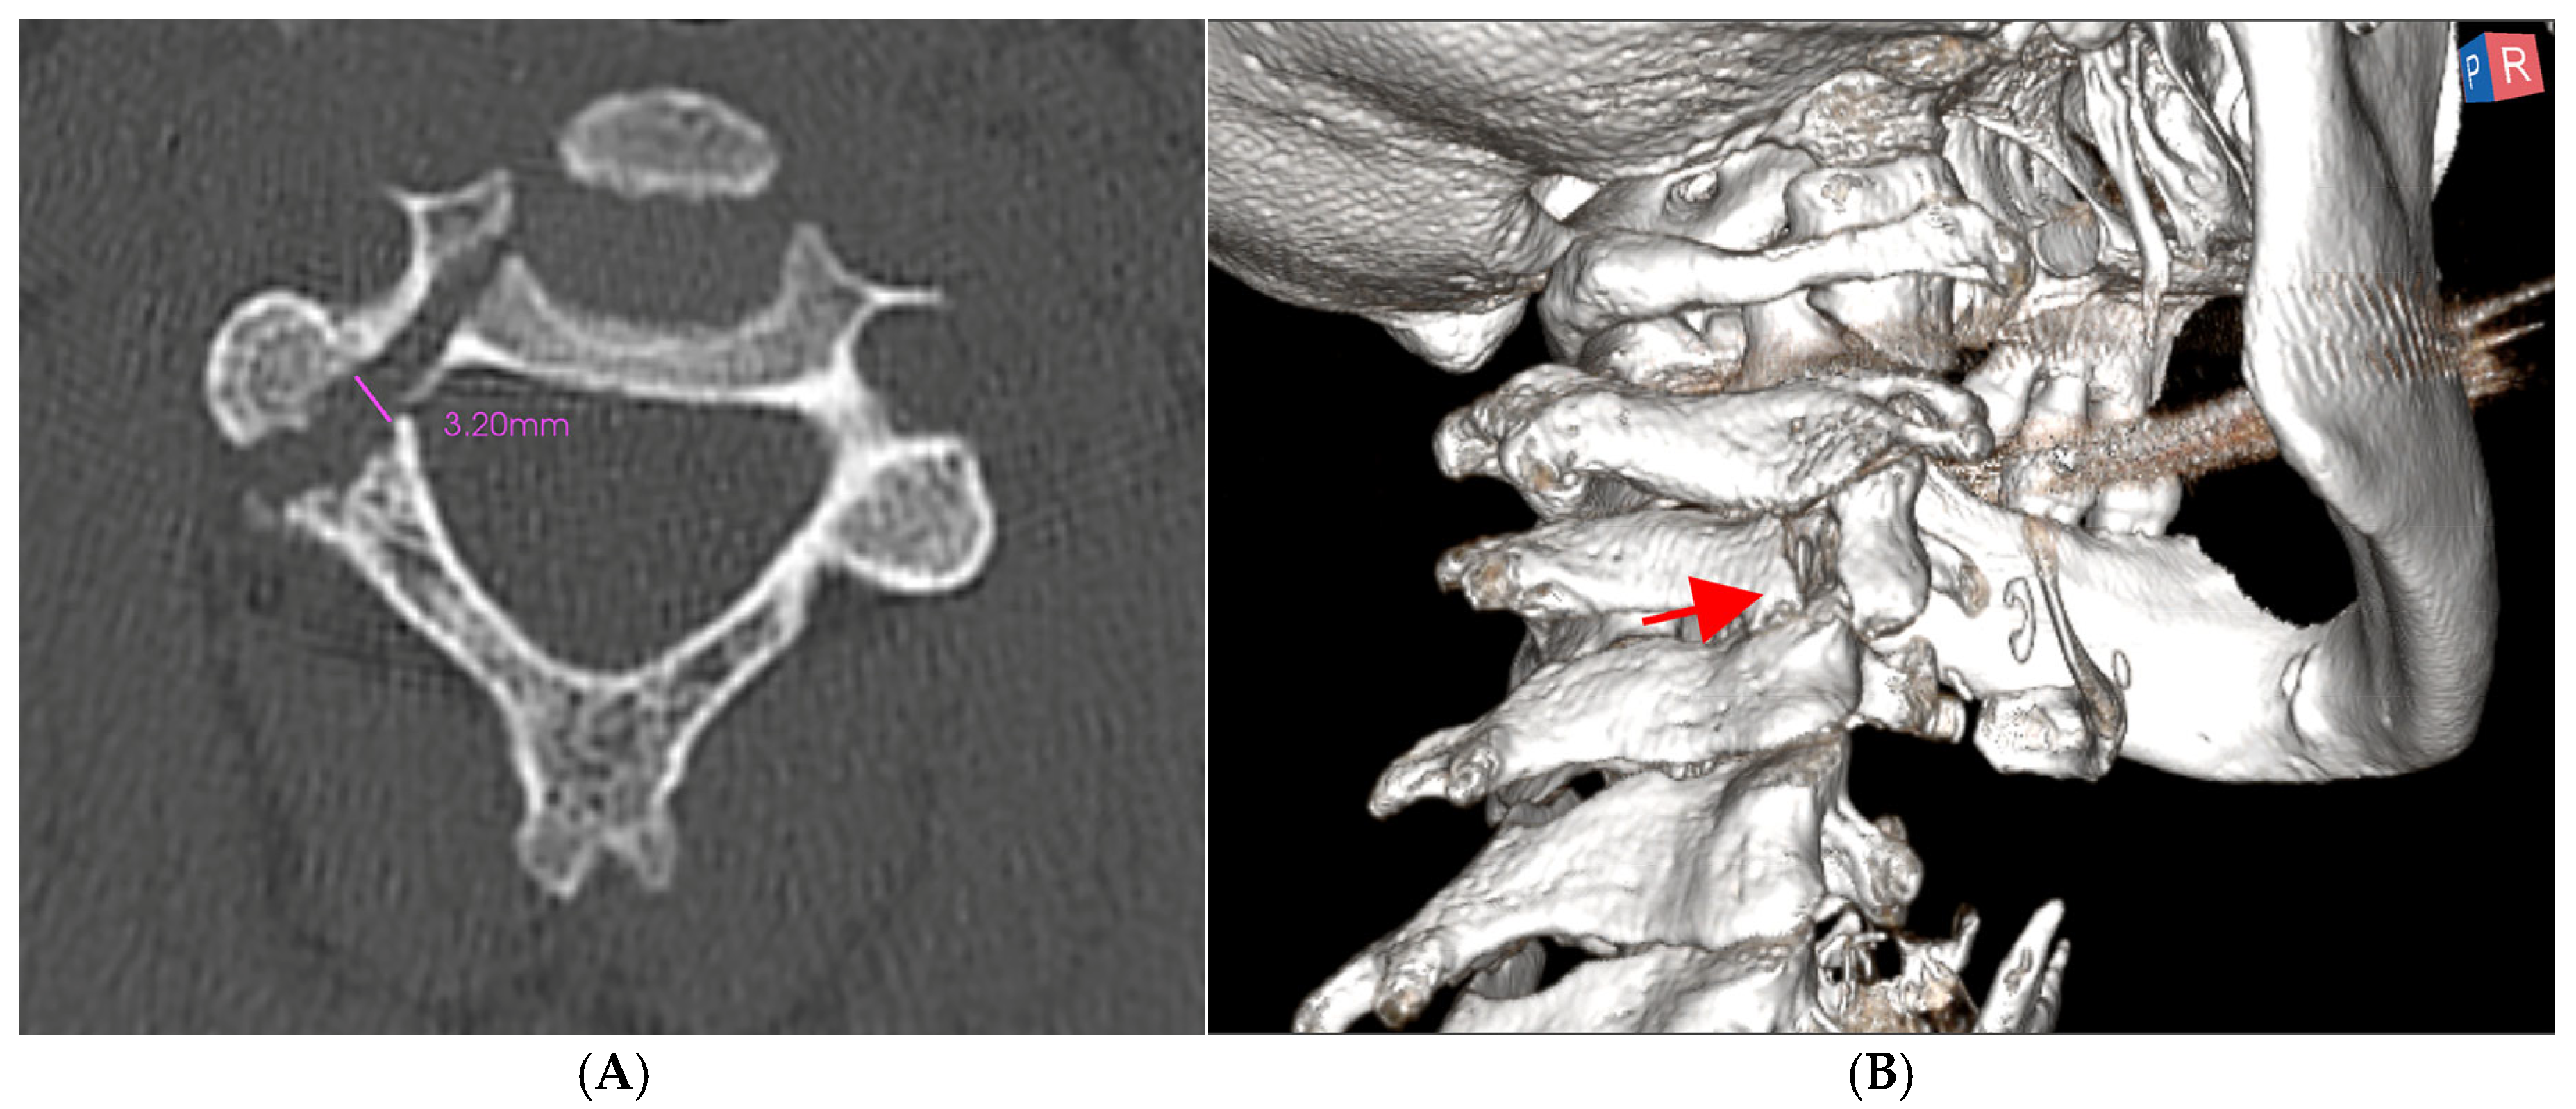

2.2. Surgical Technique

3. Results